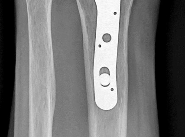

Question 18:

A 35-year-old farmer sustains an open midshaft tibia fracture when a tractor rolls over his leg. The wound is 12 cm long with significant contamination, including soil and manure. According to standard orthopedic trauma guidelines, what is the most appropriate prophylactic intravenous antibiotic regimen?

Correct Answer: First-generation cephalosporin, an aminoglycoside, and high-dose penicillin

Explanation:

This is a Gustilo-Anderson Type III open fracture occurring in a farming environment. The standard antibiotic protocol for a Type III open fracture includes a first-generation cephalosporin (for Gram-positive coverage) and an aminoglycoside (for Gram-negative coverage). However, when the wound is heavily contaminated with soil, manure, or standing water (e.g., farm injuries), the addition of high-dose penicillin is indicated to provide coverage against anaerobic organisms, particularly Clostridium species, to prevent gas gangrene.